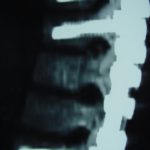

Εικ. 4: Μετεγχειρητική προσθιοπίσθια (α) και πλαγία (β) ακτινογραφία της θωρακο-οσφυικής μοίρας της σπονδυλικής στήλης.

Παρατηρείται η σταθεροποίηση της σπονδυλικής στήλης με σύστημα διαυχενικών κοχλιών και ράβδων.